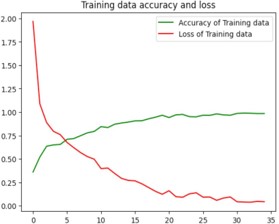

Model training

Python code has been used for the training and testing process. The code contains several libraries such as tensorflow, numpy, matplotlib, keras which is a higher-level neural networks API that comes integrated with tensorflow [1]. The loading of the training and test datasets is done using tf.keras.preprocessing.image_dataset_from_directory(). A neural network model with multiple layers is created using keras that contains convolutional, Max-pooling, Dropout and Dense layers. Sparse categorical cross-entropy loss function and Adam optimizer are used to build the model. The training process is run for 35 epochs as shown in figure 8. The loss and accuracy gained is plotted and the visualization of the test images and predictions are made which was displayed in figure9. Finally, the trained model is stored as “ALZ.h5 ‘’ in HDF5 format [12].

Image preprocessing and feature extraction is done based on the brightness, texture, dimension etc. Using thresholding, Augmentation, Gray scaling [13]. DL techniques and algorithms have been used for training the model, identification and classification of the Image. The results show that the trained model produces 98.02% accuracy in the prediction of the disease and classification is given as output when the input, that is MRI of the Brain is fed to the system.